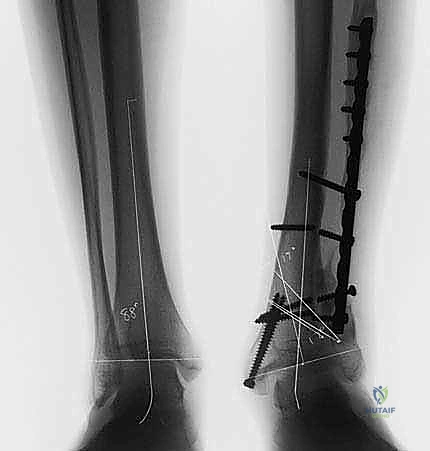

يتم إجراء صور أشعة سينية خاصة (طويلة للساق بالكامل أثناء الوقوف) وأشعة مقطعية (CT Scan) ثلاثية الأبعاد. يقوم الدكتور محمد هطيف باستخدام برامج حاسوبية متقدمة لحساب الزاوية الدقيقة للتشوه، وتحديد حجم "الوتد العظمي" (Bone Wedge) الذي يجب إزالته أو إضافته لإصلاح المحور.

5. التثبيت الداخلي القوي (Internal Fixation)

بعد الوصول للزاوية المثالية التي تم حسابها مسبقاً، يتم تثبيت العظم بإحكام شديد باستخدام شرائح معدنية متطورة (Locking Plates) ومسامير من التيتانيوم. هذا التثبيت القوي هو ما يسمح للمريض ببدء الحركة والتأهيل مبكراً.

الحالة الأولى: تصحيح تشوه ما بعد كسر قديم

مريض يبلغ من العمر 42 عاماً، تعرض لكسر في الساق قبل 5 سنوات التئم بشكل خاطئ، مما أدى إلى تقوس شديد للداخل (Varus) وألم مستمر يمنعه من العمل. بعد تقييم دقيق من قبل الأستاذ الدكتور محمد هطيف، تم إجراء جراحة قطع عظم الساق فوق الكاحل بتقنية الوتد المفتوح. بعد 4 أشهر من الجراحة والتأهيل، عاد المريض لعمله الميداني بمحور ساق مستقيم تماماً وبدون أي ألم.